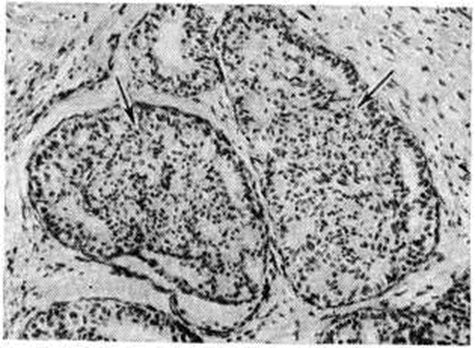

Рис. 2.

Микропрепарат молочной железы при пролиферативной мастопатии: криброзные и солидные внутрипротоковые разрастания указаны стрелками: окраска гематоксилин-эозином; × 250.

Пролиферативная форма Мастопатия характеризуется сочетанием различных вариантов эпителиальной, миоэпителиальной и фиброэпителиальной пролиферации. При эпителиальной пролиферации возникают аденит или мазоплазия (физиологический гиперплазия долек с начальными патологический изменениями) с резко увеличенными, правильно сформированными железистыми дольками. В поздних стадиях Мастопатия на фоне этих изменений обнаруживаются другие морфологический проявления процесса: кисты, цистаденопапилломы и другие При другом варианте эпителиальной пролиферации отмечаются разрастания протокового и долькового эпителия. Возникающие при этом внутрипротоковые пролифераты имеют вид сосочков, криброзных разрастаний и солидных полей, образованных мономорфным, иногда двухрядным, цилиндрическим эпителием с признаками секреции (рисунок 2). Пролиферация внутридолькового эпителия приводит к образованию многослойной эпителиальной выстилки. Внутрипротоковые и дольковые пролифераты склонны к малигнизации и расцениваются большинством авторов как предраковые изменения.